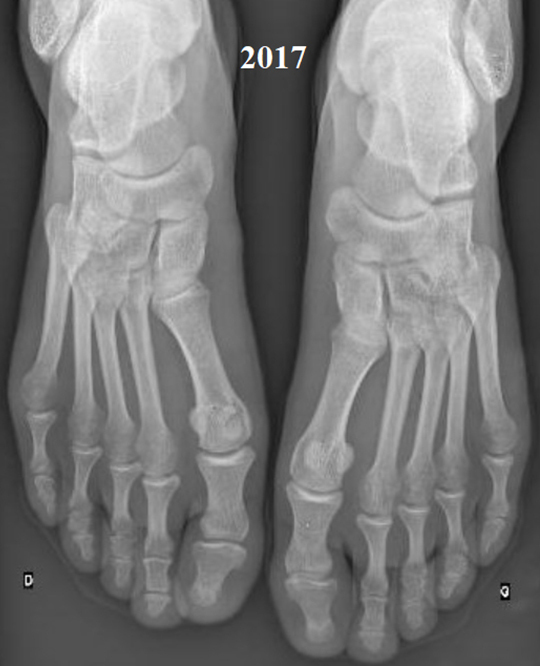

Elle vous montre sa dernière prise de sang avec une protéine C réactive (CRP) à 45 mg/L et vous apporte ses dernières radiographies (fig. 2), que vous comparez aux précédentes (fig. 1).

Figure 2 (Source Salomé Abdellaoui, La Revue du Praticien)

On observe sur la radiographie de 2024 un pincement articulaire de toutes les articulations métatarso-phalangiennes avec des subluxations de ces dernières et des érosions de la tête des 5es métatarsiens, caractéristiques de la polyarthrite rhumatoïde.

La polyarthrite rhumatoïde n’est pas contrôlée et est sévère avec une aggravation structurale, il y a une indication à intensifier le traitement pour préserver les articulations.